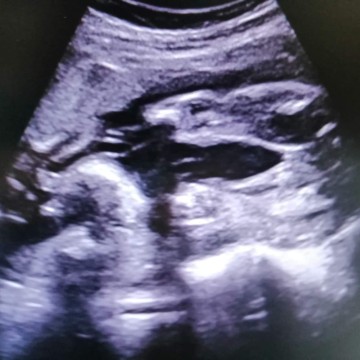

แม่ๆช่วยบอกเพศให้หน่อยได้ไหมค่ะ

เมื่อเดือนที่แล้วหมอบอกผู้ชาย80%เดือนนี้หมอบอกผู้หญิงอยากให้แม่ช่วยดูให้ว่าหญิงหรือชายกันแน่เป็นคุณแม่มือใหม่ค่ะ

น่าจะหญิงนะคะ จู๋ไม่โผล่